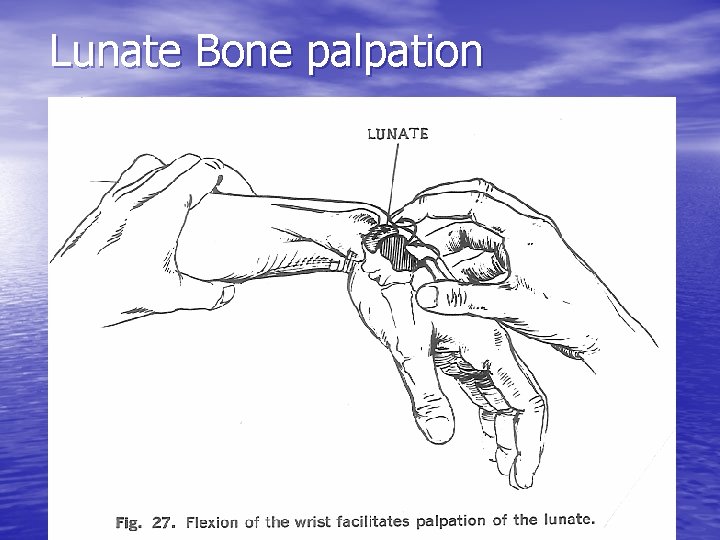

Lunate Bone palpation